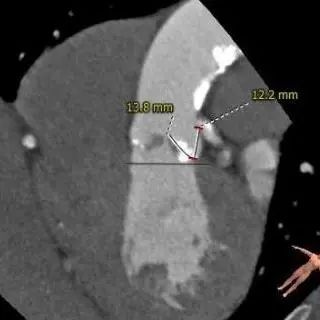

主动脉根部测量

冠脉高度、瓣叶长度测量

瓣环上多平面测量